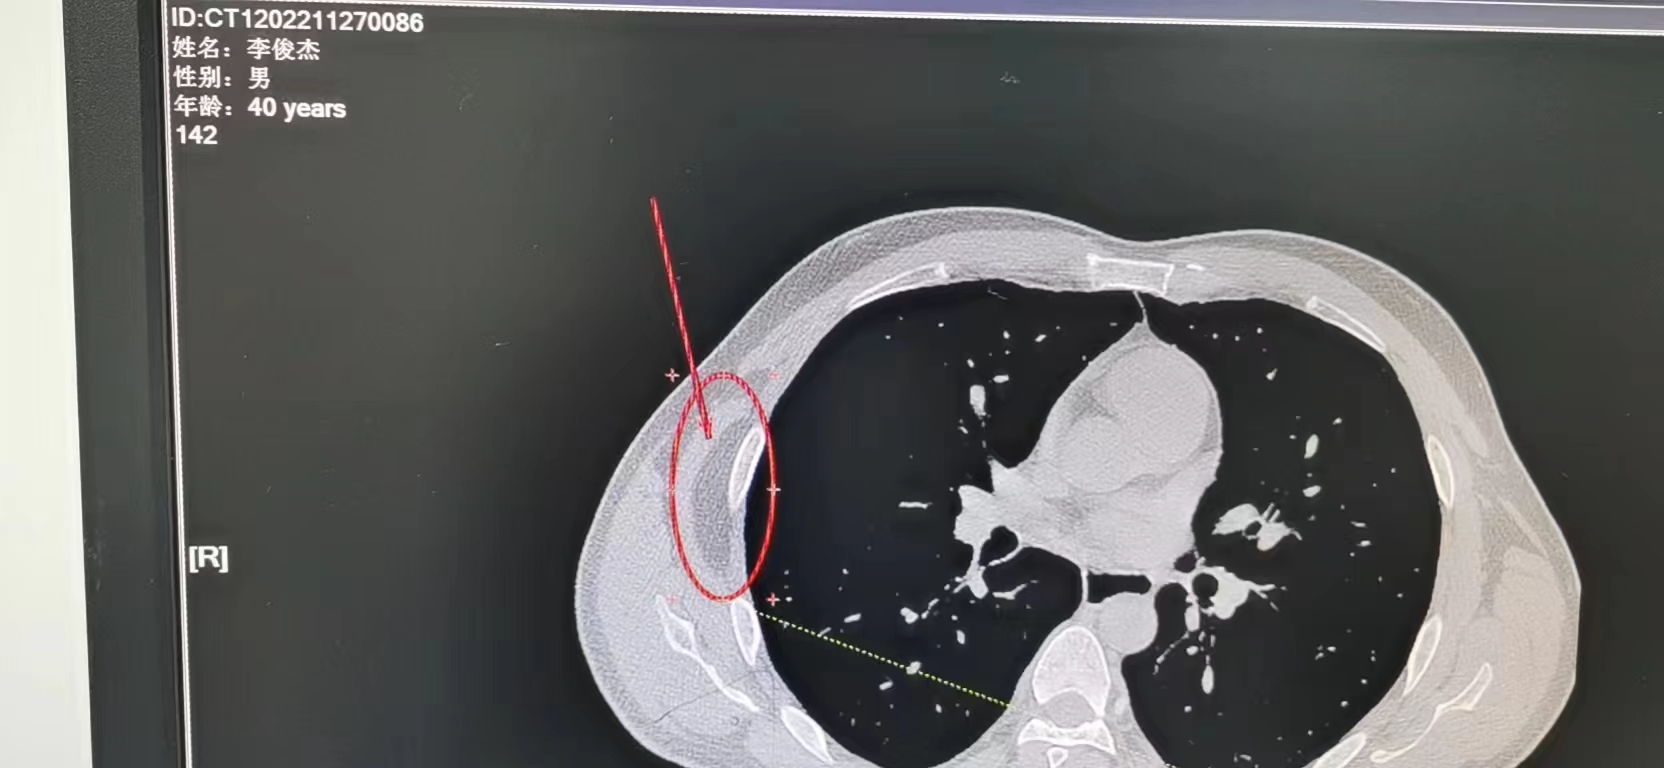

医生消毒后打了一针麻药,做的时候能感觉到电刀的阵痛,还能听到类似烧电焊时那种吱吱的声音。因脂肪瘤的位置比较深,并夹在胸部两根骨头之间,手术做到一半的时候,为了稳妥医生加了麻药剂量。脂肪瘤和肌肉粘得很紧,手术的过程感觉就像一盒抽纸比较紧的时候,慢慢地把纸张从里面抽出来,与做背上皮腺囊肿手术时“拔萝卜”是两个概念。

由于是局部麻醉,头脑很清晰,做的过程还和医生聊天。感觉没有过多久,可结束时问医生说大约花了一小时。我问医生脂肪瘤有没有大拇指手指头那么大,医生回答不止那么大。给我看时吓了一跳,金黄色的块状物,差不多手掌那么大,很像屠夫卖的猪板油,表面光滑没有泡泡。医生用手裹起来,大概有鸡蛋那么大一团。用手摸皮肤鼓了一个包,看来只是冰山一角,原来下面还藏着这么多。